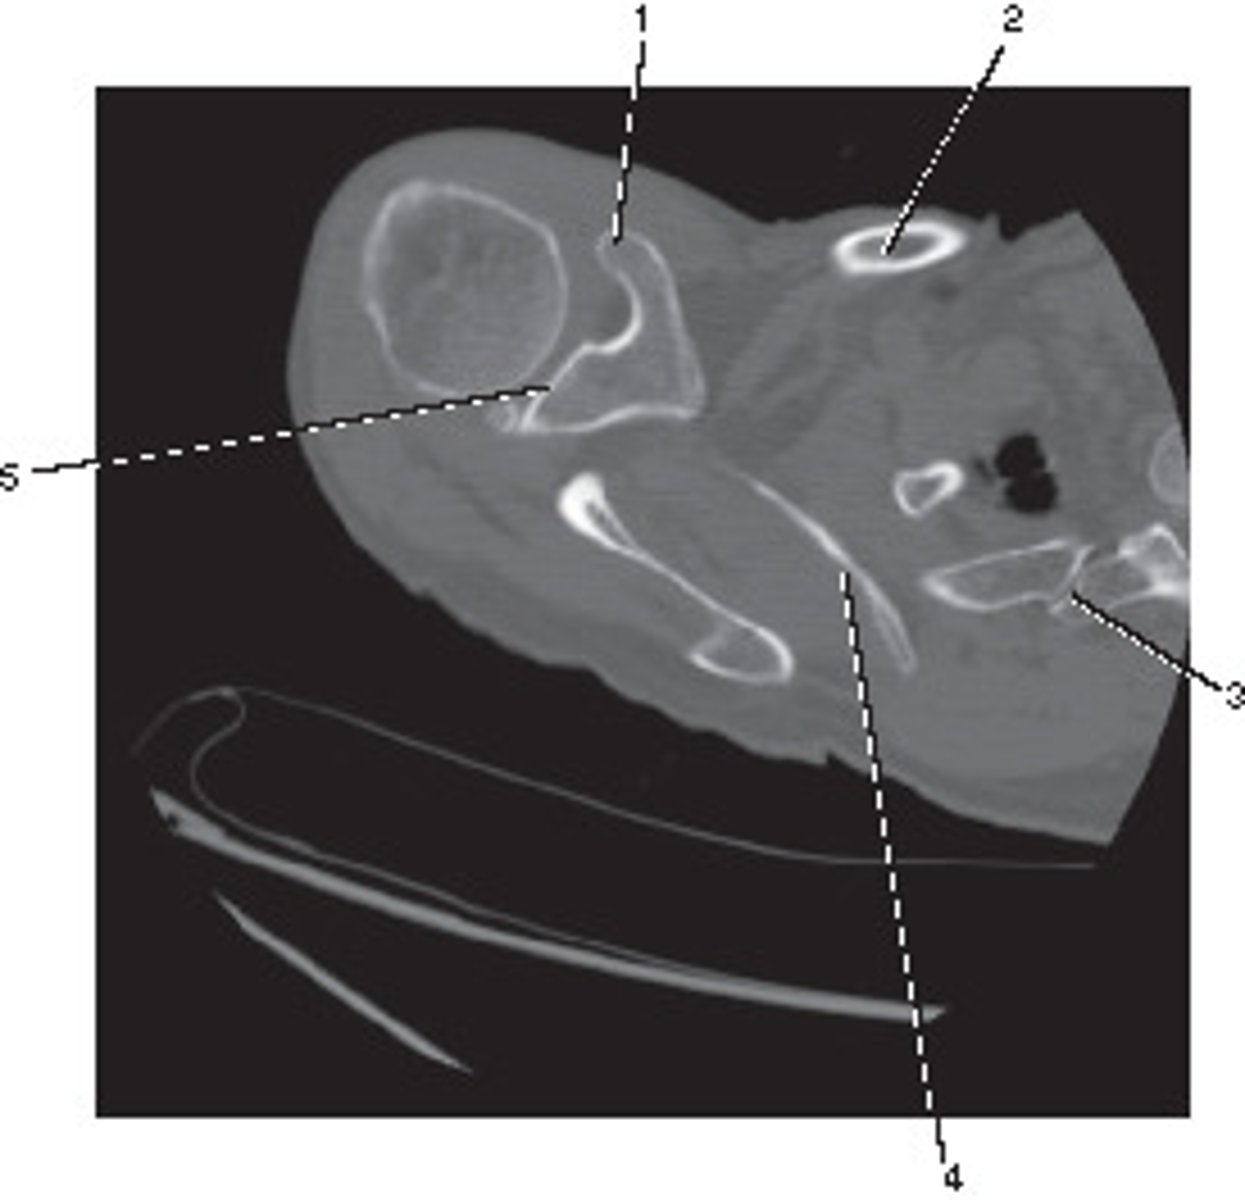

Number 2 corresponds to which of the following?

<p>Number 2 corresponds to which of the following?</p>

Number 5 corresponds to which of the following?

<p>Number 5 corresponds to which of the following?</p>

Number 3 corresponds to which of the following?

<p>Number 3 corresponds to which of the following?</p>

Which number corresponds to the vestibule?

<p>Which number corresponds to the vestibule?</p>